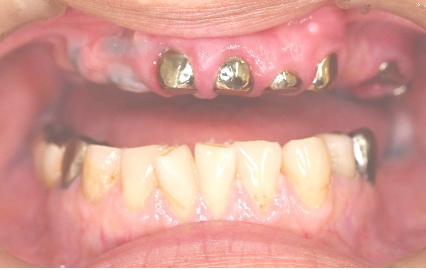

「上の前歯のブリッジが取れてしまいました。」とHさん(60歳代男性)が来院されました。お口の中を見ると、ブリッジを支える歯がすべてひどいむし歯になっており、ブリッジをセメントで簡単に付け直すことができるような状態ではありませんでした。

こうなってしまうと、もうブリッジはできません。選択肢は、

①金属バネが目立つ保険の入れ歯

②インプラント

③磁石でくっつける入れ歯(マグネット式入れ歯)

の3種類になります。Hさんは嘔吐反射が出やすいので、保険の入れ歯は避けたいとのこと。インプラントは高額で手術にも少し不安があるご様子だったので、マグネット式入れ歯をご説明しました。

Hさんは最終的に、マグネット式入れ歯を選択されました。

治療後、「入れ歯を作るとき、とても細かい治療や検査をしていただいたおかげで、ぴったりの入れ歯になったように思います。ありがとうございます。」と、とても喜んでくださいました。マグネット式入れ歯になって、何でも食べられるようになったそうです。

もし保険の入れ歯を選んだら、入れ歯のバネをかける歯から順に抜けていき、最終的には総入れ歯になってしまう可能性が高かったと思います。また、Hさんの場合は、インプラント治療の3分の1ほどの費用で済んだため、費用面での負担も抑えられたと思います。マグネット式入れ歯は、残りの歯が少なくなった時に有効な治療法です。